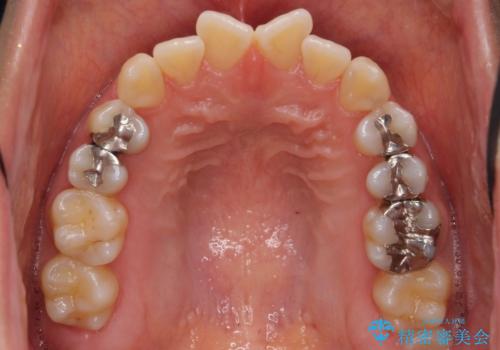

前歯のがたつき 若干受け口 インビザラインで

治療症例の内容

- 前歯のねじれおよび下の前歯が前に出ていることを気にして来院。

インビザラインで治療をおこないました。

前歯のねじれもなおり、比較的短期間でご満足いただけました。

部分矯正コースでしたので左下67の段差は特に治しておりません。

右下567及び左下6の虫歯治療も一緒に行っています。